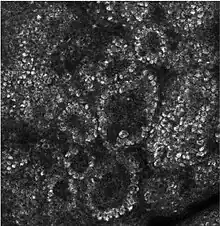

Cell boundaries

Epidermal cells are tightly interconnected to serve as a tight barrier against the exterior environment. The junctions between the epidermal cells are of the adherens junction type, formed by transmembrane proteins called cadherins. Inside the cell, the cadherins are linked to actin filaments. In immunofluorescence microscopy, the actin filament network appears as a thick border surrounding the cells,[9] although the actin filaments are actually located inside the cell and run parallel to the cell membrane. Because of the proximity of the neighboring cells and tightness of the junctions, the actin immunofluorescence appears as a border between cells.[9]